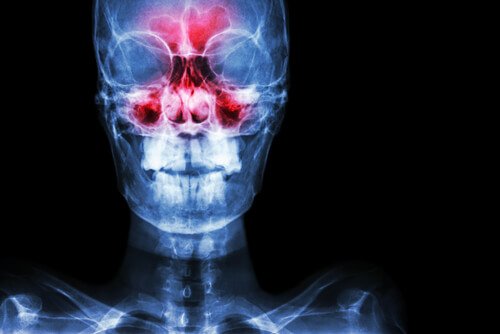

Симптоми синуситу: від розвитку до діагностики

Синусит є запаленням навколоносових пазух – двох невеликих порожнин, куди потрапляє повітря, що циркулює між кістками носа. Ми рекомендуємо звернути особливу увагу на симптоми синуситу для того, щоб мати змогу діагностувати захворювання на ранніх стадіях.

Є чотири різні групи пазух: лобові, комірки решітчастого лабіринту, клиновидні та гайморові.

Зазвичай синусит можна діагностувати за умови обстеження стану носа. Лікар може посвітити у носові отвори ліхтариком, шукаючи поліпи або інші ознаки запального процесу. Також варто трохи натиснути на ніс та область навколо нього, щоб перевірити, чи немає у хворого больових відчуттів. Саме біль допоможе підтвердити або спростувати діагноз “синусит”.

З метою встановлення правильного діагнозу лікар може призначити такі аналізи: риноскопія, комп’ютерна томографія або магнітно-резонансне обстеження. Зверніть увагу, що рентген дуже рідко дає правдиві результати у цьому випадку.